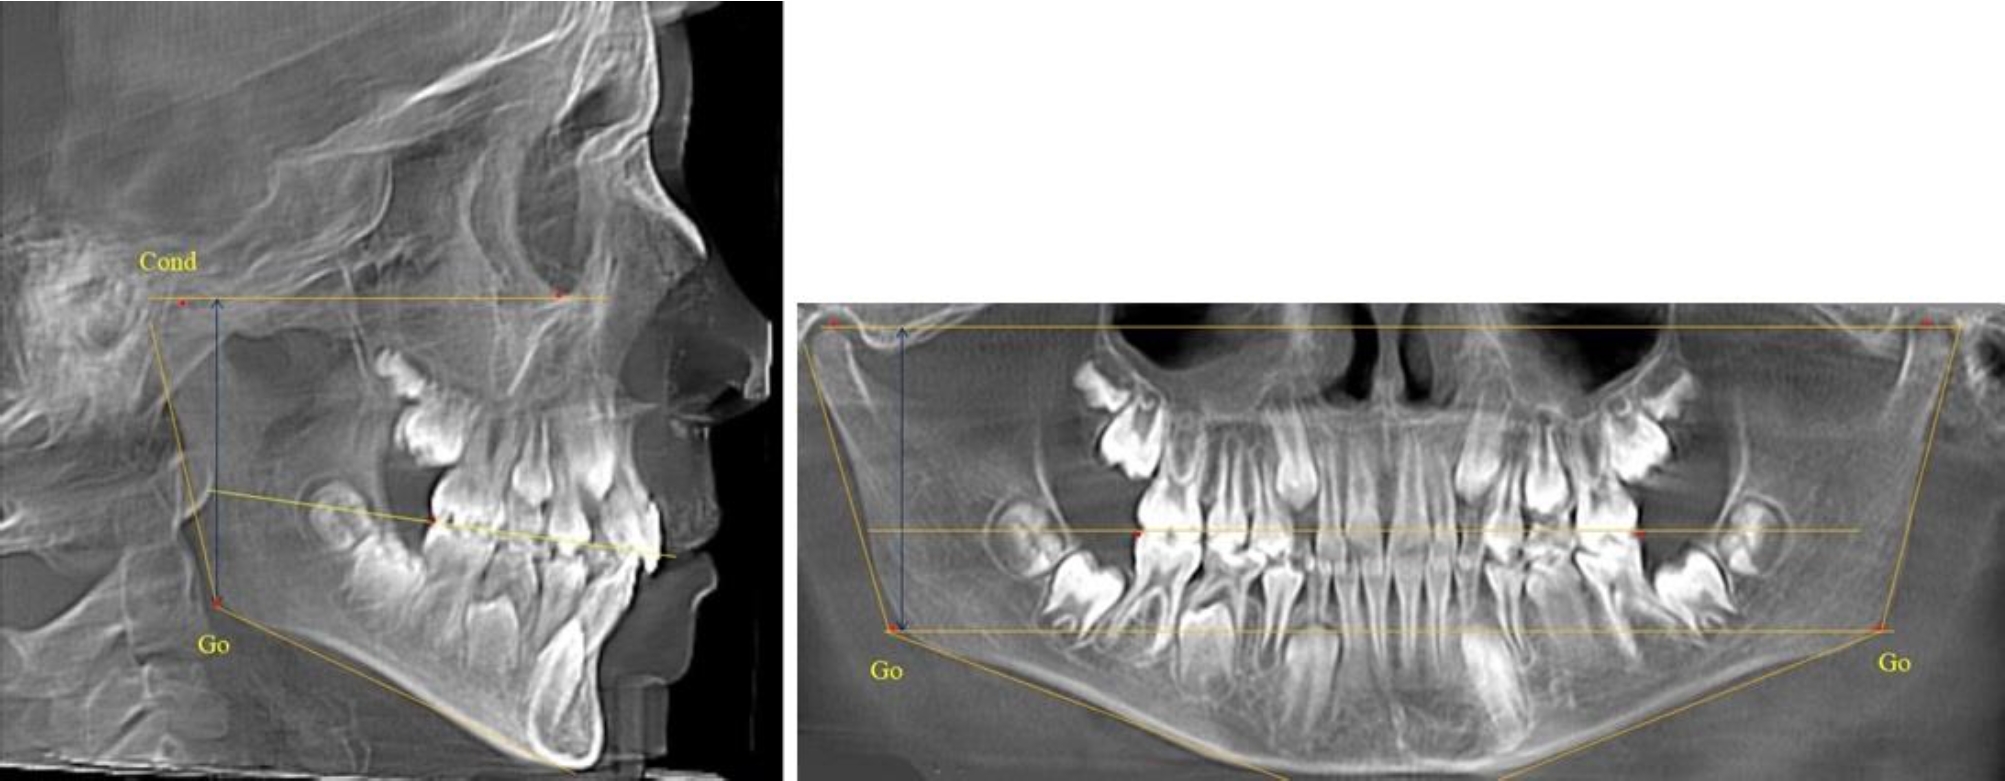

В 1-й группе были проанализированы 7 телерентгенограмм и 7 ортопантомограмм, что составило (6,60 ± 2,41) % от числа изученных рентгенограмм. На всех парах рентгенограмм угол нижней челюсти, измеренный на телерентгенограмме, соответствовал углу, полученному при построении угла на ортопантомограмме. Окклюзионная линия практически однотипно делила ветвь на два отдела (рис. 1).

Как на ортопантомограмме, так и на телерентгенограмме высота ветви у детей в периоде сформированного прикуса молочных зубов составляла (42,21 ± 2,48) мм. При этом высота верхней окклюзионно-суставной части была (22,57 ± 1,46) мм, а нижней – (19,64 ± 1,54) мм.

Учитывая вариабельность абсолютных величин, определи относительные показатели соразмерности частей ветви нижней челюсти. Так, отношение высоты верхней части ветви к нижней в среднем составляло 1,15 ± 0,13. Отношение общей высоты ветви к верхней ее части составляло 1,87 ± 0,14, а отношение общей высоты ветви к нижней ее части было 2,14 ± 0,16 и достоверных различий по относительному показателю отношения всей высоты к верхней и нижней челюсти нами не отмечено (р ˃ 0,05). При этом визуально обе части выглядели примерно равноразмерными.

Рис. 1. ТРГ и ОПТГ пациента 1-й группы

Рис. 2. ТРГ и ОПТГ пациента после прорезывания первых постоянных моляров